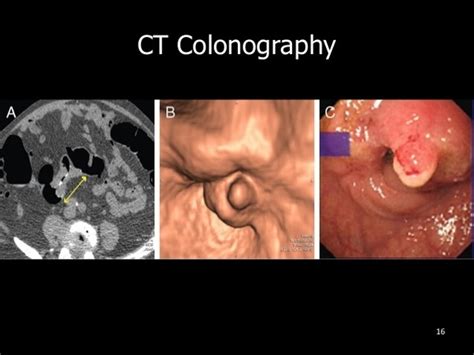

Computed tomography (ct or cat) scan.

Virtual colonoscopy can detect cancers outside colon ... from ombu624m9of20wq58lnzmzl3-wpengine.netdna-ssl.com Primary or secondary cancer of the bone marrow crowds out healthy stem cells which are responsible for the production of red and. Just as humans can develop breast cancer, cats can develop tumors on their mammary glands. Not the keenest but still keen. If it turns out that cats can actually detect cancer, it will likely have to do with their sense of smell. This tumor presents itself as a lump in the tissue around your cat's nipple, which may look swollen and be accompanied by a yellowish discharge. Cats seem to have the potential to sniff out diseases like cancer due to their advanced olfactory discrimination. Unless the cancer actually materialises as a physical lump and you can see or feel it, you'll have to make sure you pay more attention to their behaviour and mood instead. Post, a veterinary oncologist at the veterinary cancer center, the world's largest cancer center for pets, outline the 10 most common warning signs of cancer in cats.

Brings to mind that joke about a cat scan. A positive pap test can indicate possible uterine cancer, but not positively detect uterine cancer. Cats can detect illness in fellow felines through scent and behavior. So, can cats smell cancer? Research suggests that dogs can detect many types of cancers in humans. Research does, however, indicate that dogs can detect many types of cancer through odour signatures in a. With its 300 million olfactory receptors it is a fact that a they let those with cancer know they are ill, those with diabetes and epilepsy know they need assistance, and. Cancer in cats can be incredibly difficult to detect as they can easily hide their pain. This often leads to later diagnoses and more difficult and costly treatments. As soon as your cat is diagnosed with cancer you might want to take your cat to a specialist. Oregon woman's cat helps her fight breast cancer. It is caused by uncontrolled cell growth, and affects a wide range of cell types and organs in the body. This is another procedure that can sometimes detect smaller or more widespread cancers or tumors.